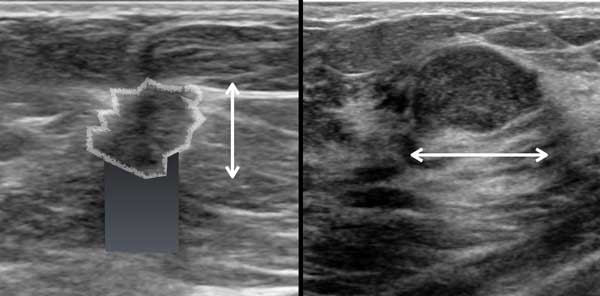

Quầng tăng âm (Hyperechoic halo)

Một dấu hiệu thường gặp trong ung thư vú là quầng tăng âm bao quanh khối giảm âm.

Quầng này là một phần của khối u và cần được tính vào kích thước đo của khối u.

Đây là hai tổn thương hình bầu dục giảm âm.

Tổn thương bên trái là ung thư biểu mô.

- Hình dạng bất thường

- Bờ góc cạnh và không rõ nét

- Quầng tăng âm xung quanh

- Hướng của tổn thương nghiêng về chiều dọc, không song song với da, tức là chiều cao lớn hơn chiều rộng

- Bóng cản âm phía sau

Tổn thương bên phải là u xơ tuyến vú.

- Hình bầu dục với múi nhẹ

- Bờ rõ nét

- Hướng nằm ngang, song song với da

- Tăng âm phía sau